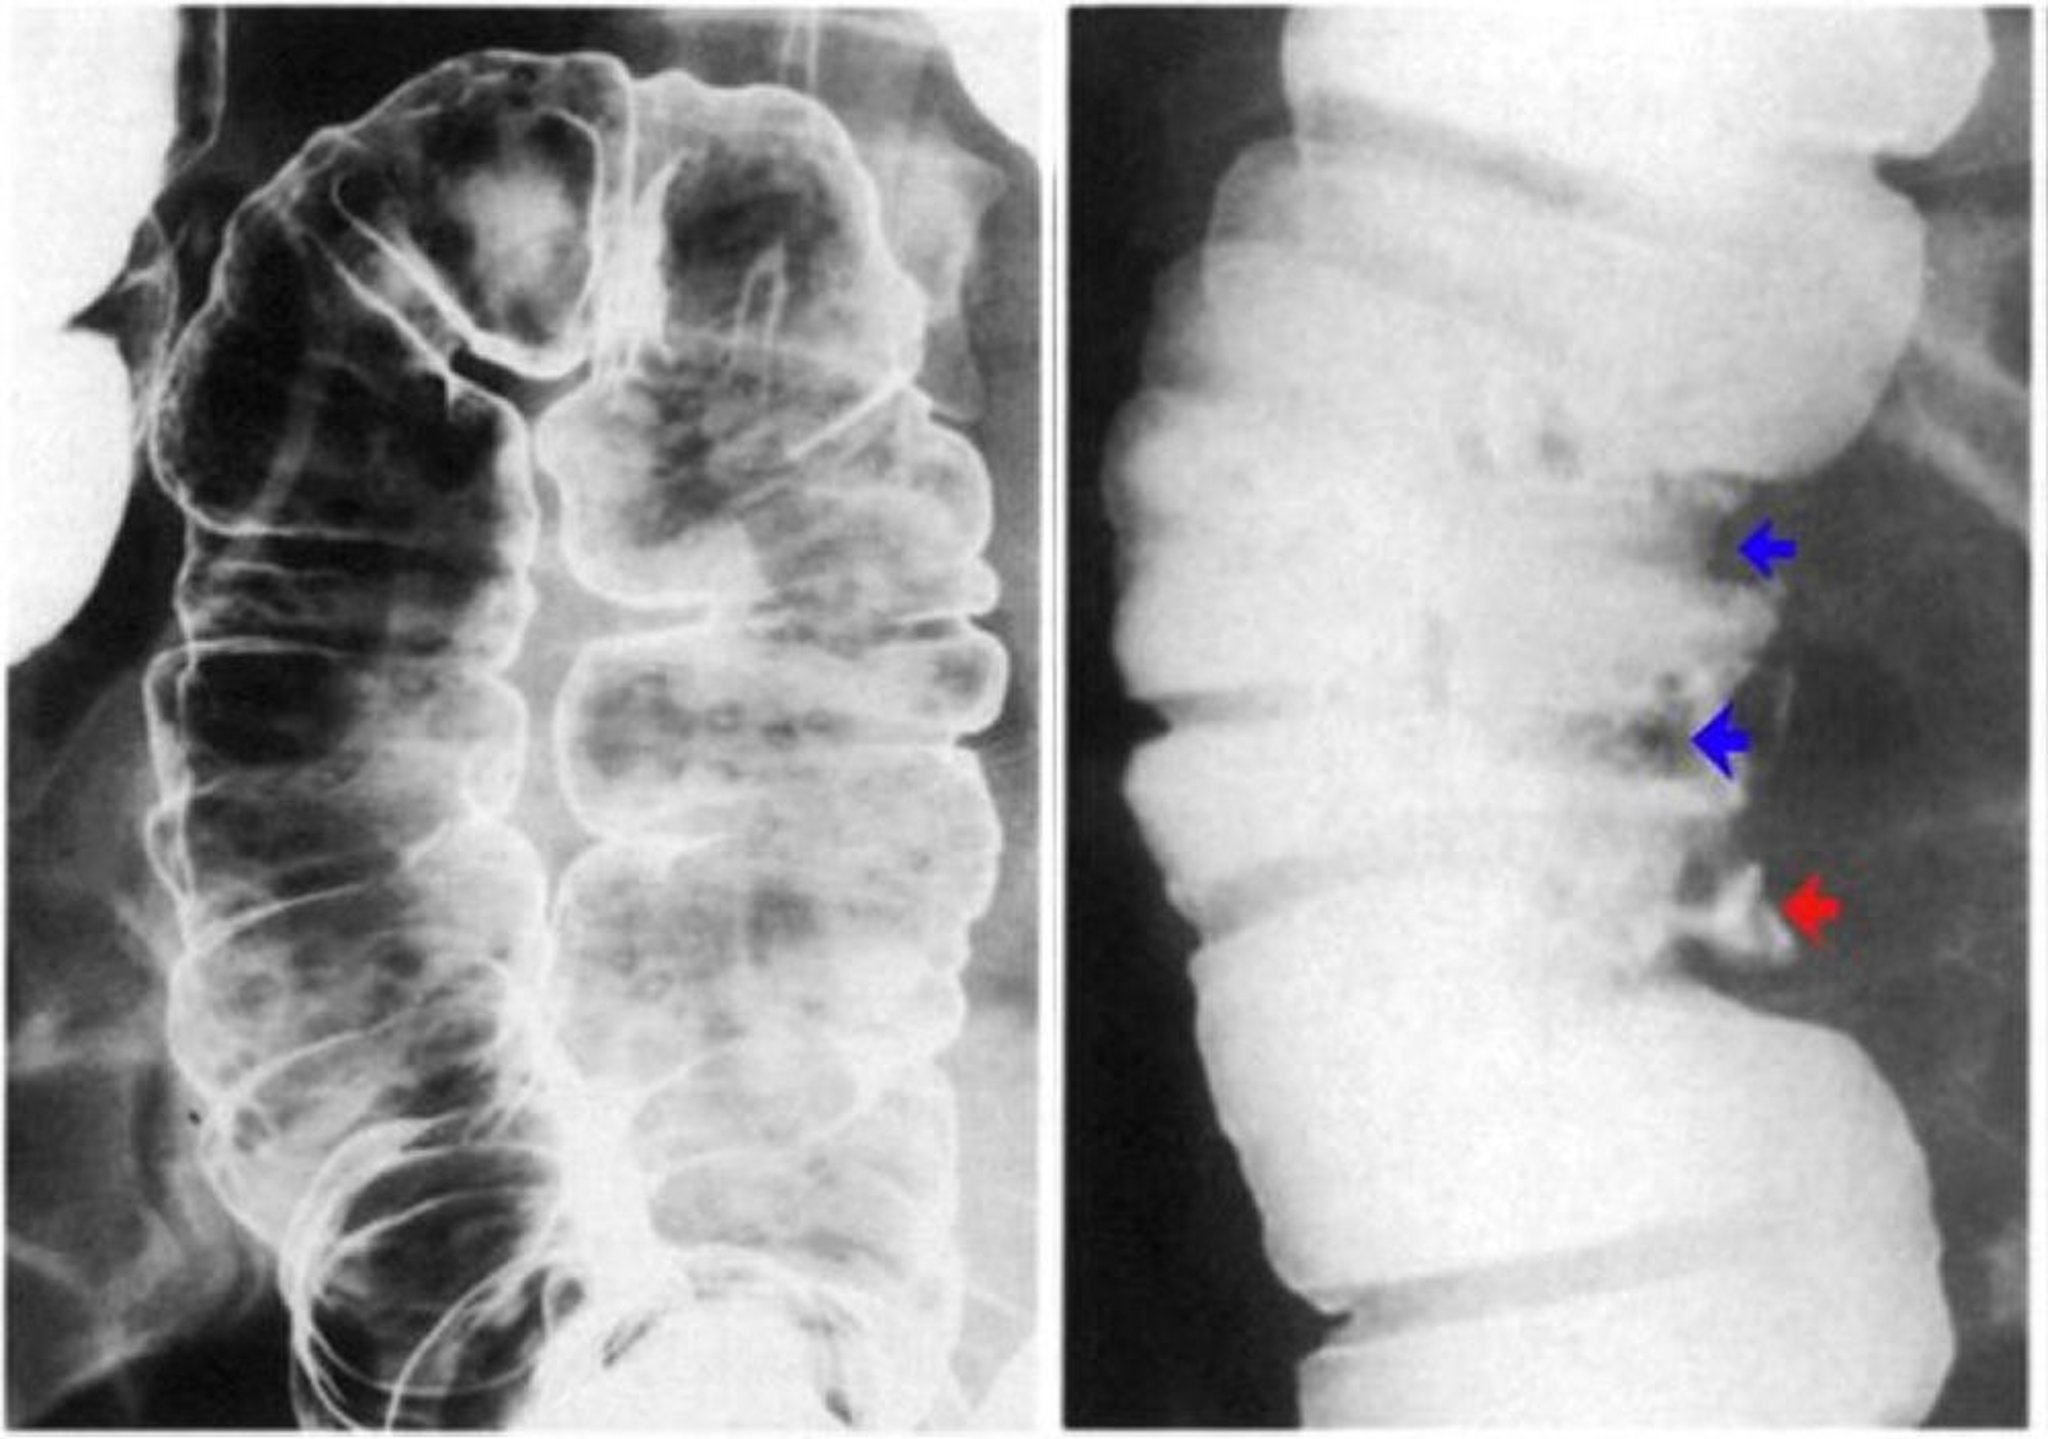

Lavement baryté montrant une ulcération de la paroi du côlon

L'image de gauche montre des ulcères aphteux. Il existe des érosions discrètes avec un halo clair sur un fond de muqueuse normale. L'image de droite montre des pseudopolypes mis en évidence par des défauts de contraste (flèches bleues) et également un ulcère profond (flèche rouge).